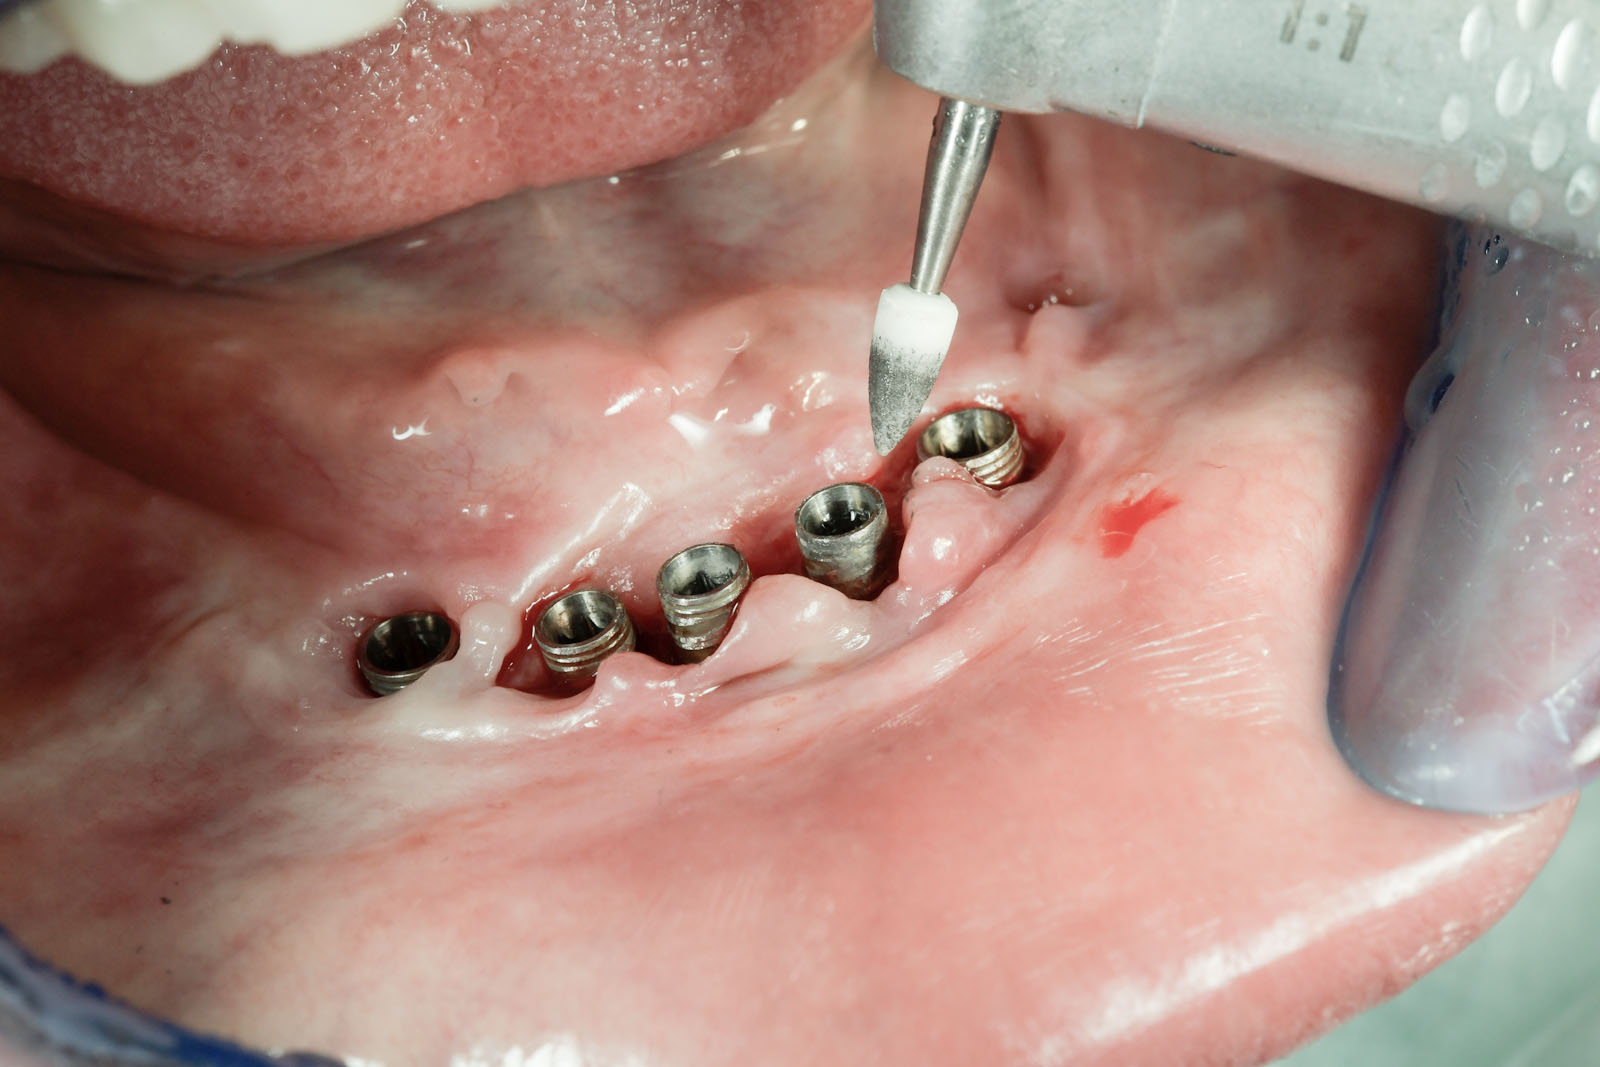

Usuwanie kamienia nazębnego (skaling) wykonywane jest mechanicznie za pomocą urządzenia ultradźwiękowego (skaler) lub precyzyjnych ręcznych narzędzi (kireta) bezpiecznych dla szkliwa. Zabieg ten jest bezbolesny i rutynowo nie wymaga znieczulenia. Tylko w niektórych przypadkach, np. przy obecności stanu zapalnego lub kamienia zlokalizowanego poddziąsłowo, dla komfortu pacjenta stosuje się znieczulenie miejscowe. W przypadku dużej ilości złogów i trudności w oczyszczaniu zabieg można rozłożyć na kilka wizyt.